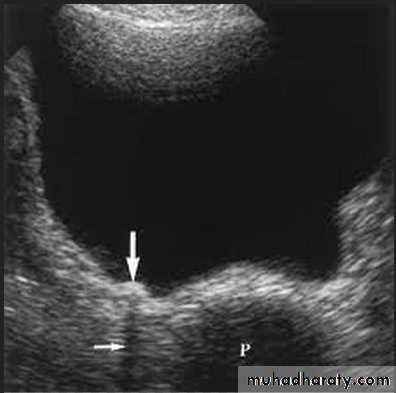

Renal ultrasound is a simple noninvasive examination .The kidney is bean shaped and has bright central echoes because of the fat surrounding the collecting system.

Normal renal ultrasound.

A longitudinal view of the right kidney was obtained by passing the sound beam through the right lobe of the liver. The kidney is seen behind this, outlined by the markers. The central bright echoes in the kidney are due to fat around the collecting system.